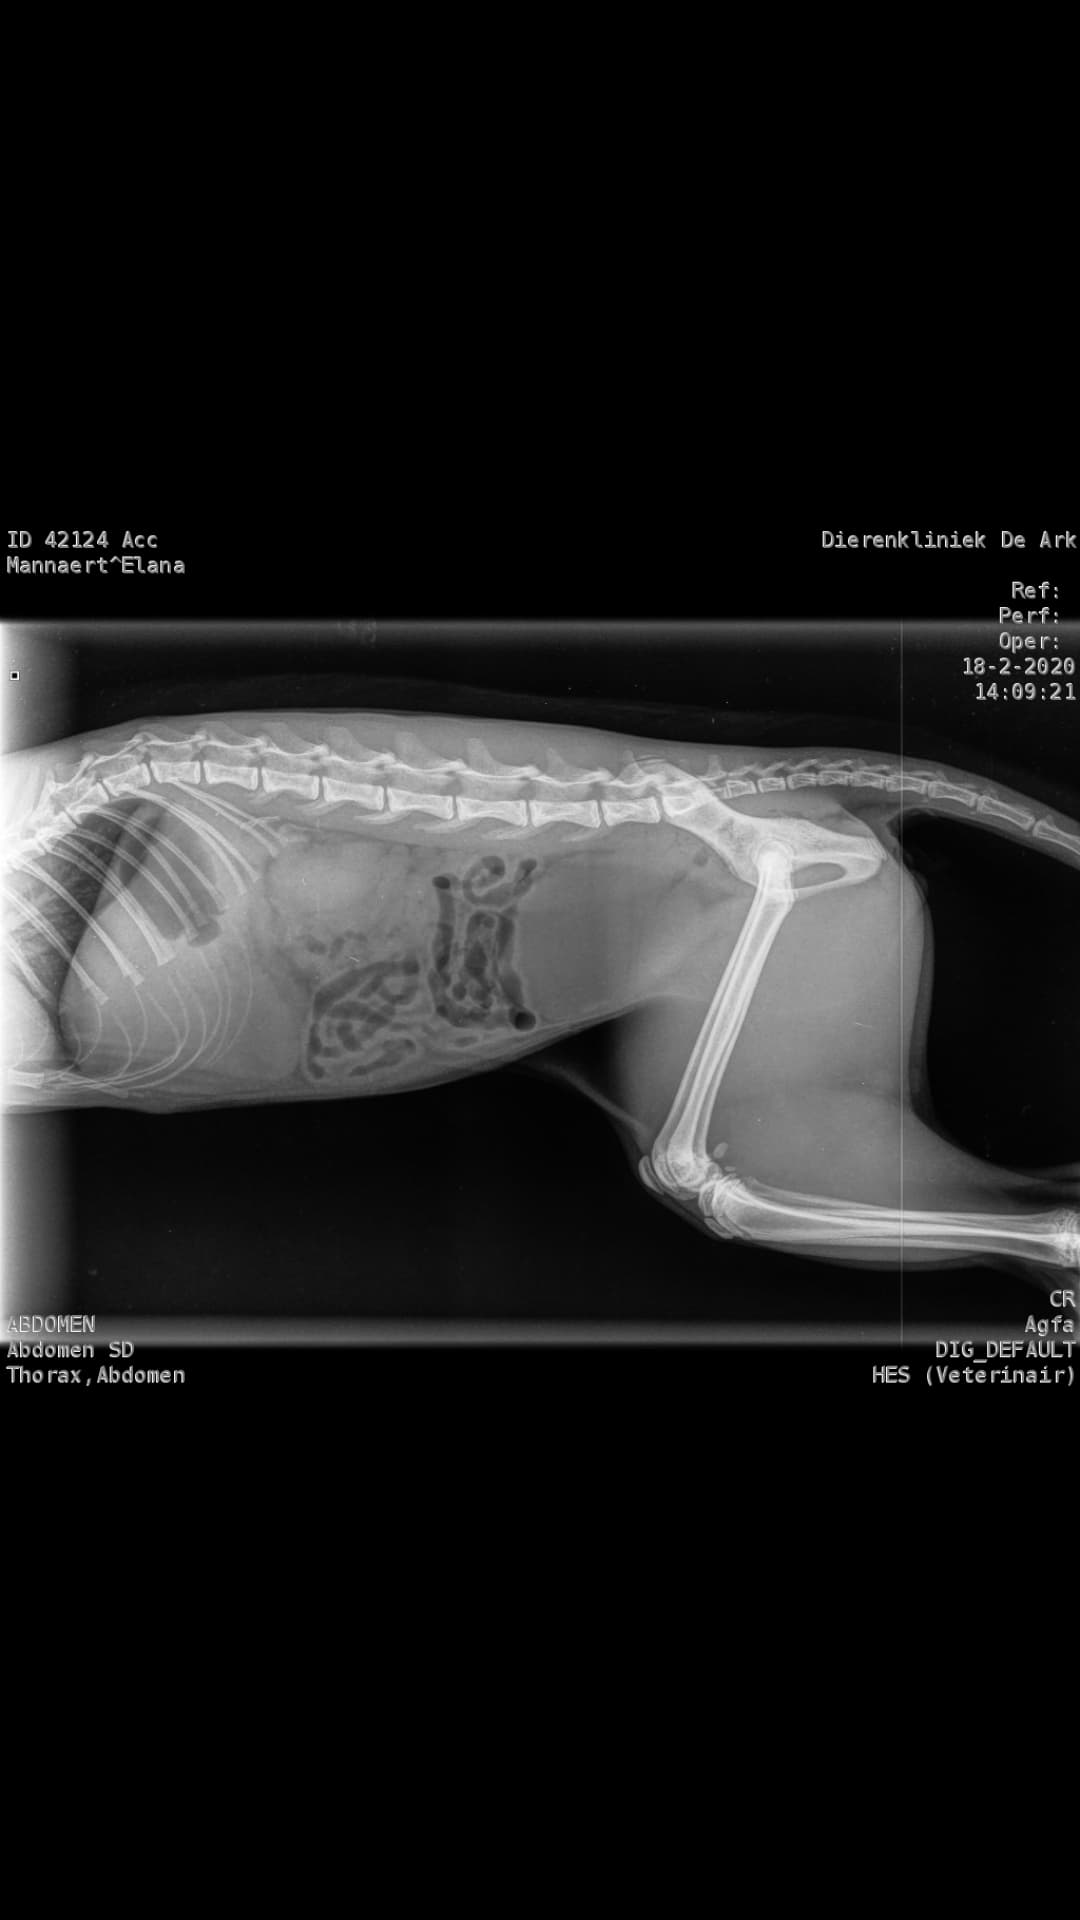

Tuesday, February 18, 2020 - 84 25 39 degrees measured at the vet. The blood tests already show that the values have changed enormously and are cause for great concern. Elana has also been fully checked. A possible accident is ruled out by means of X-rays. Her A/G values have now dropped to 0.57, this was 1.13 on day 82 of the treatment